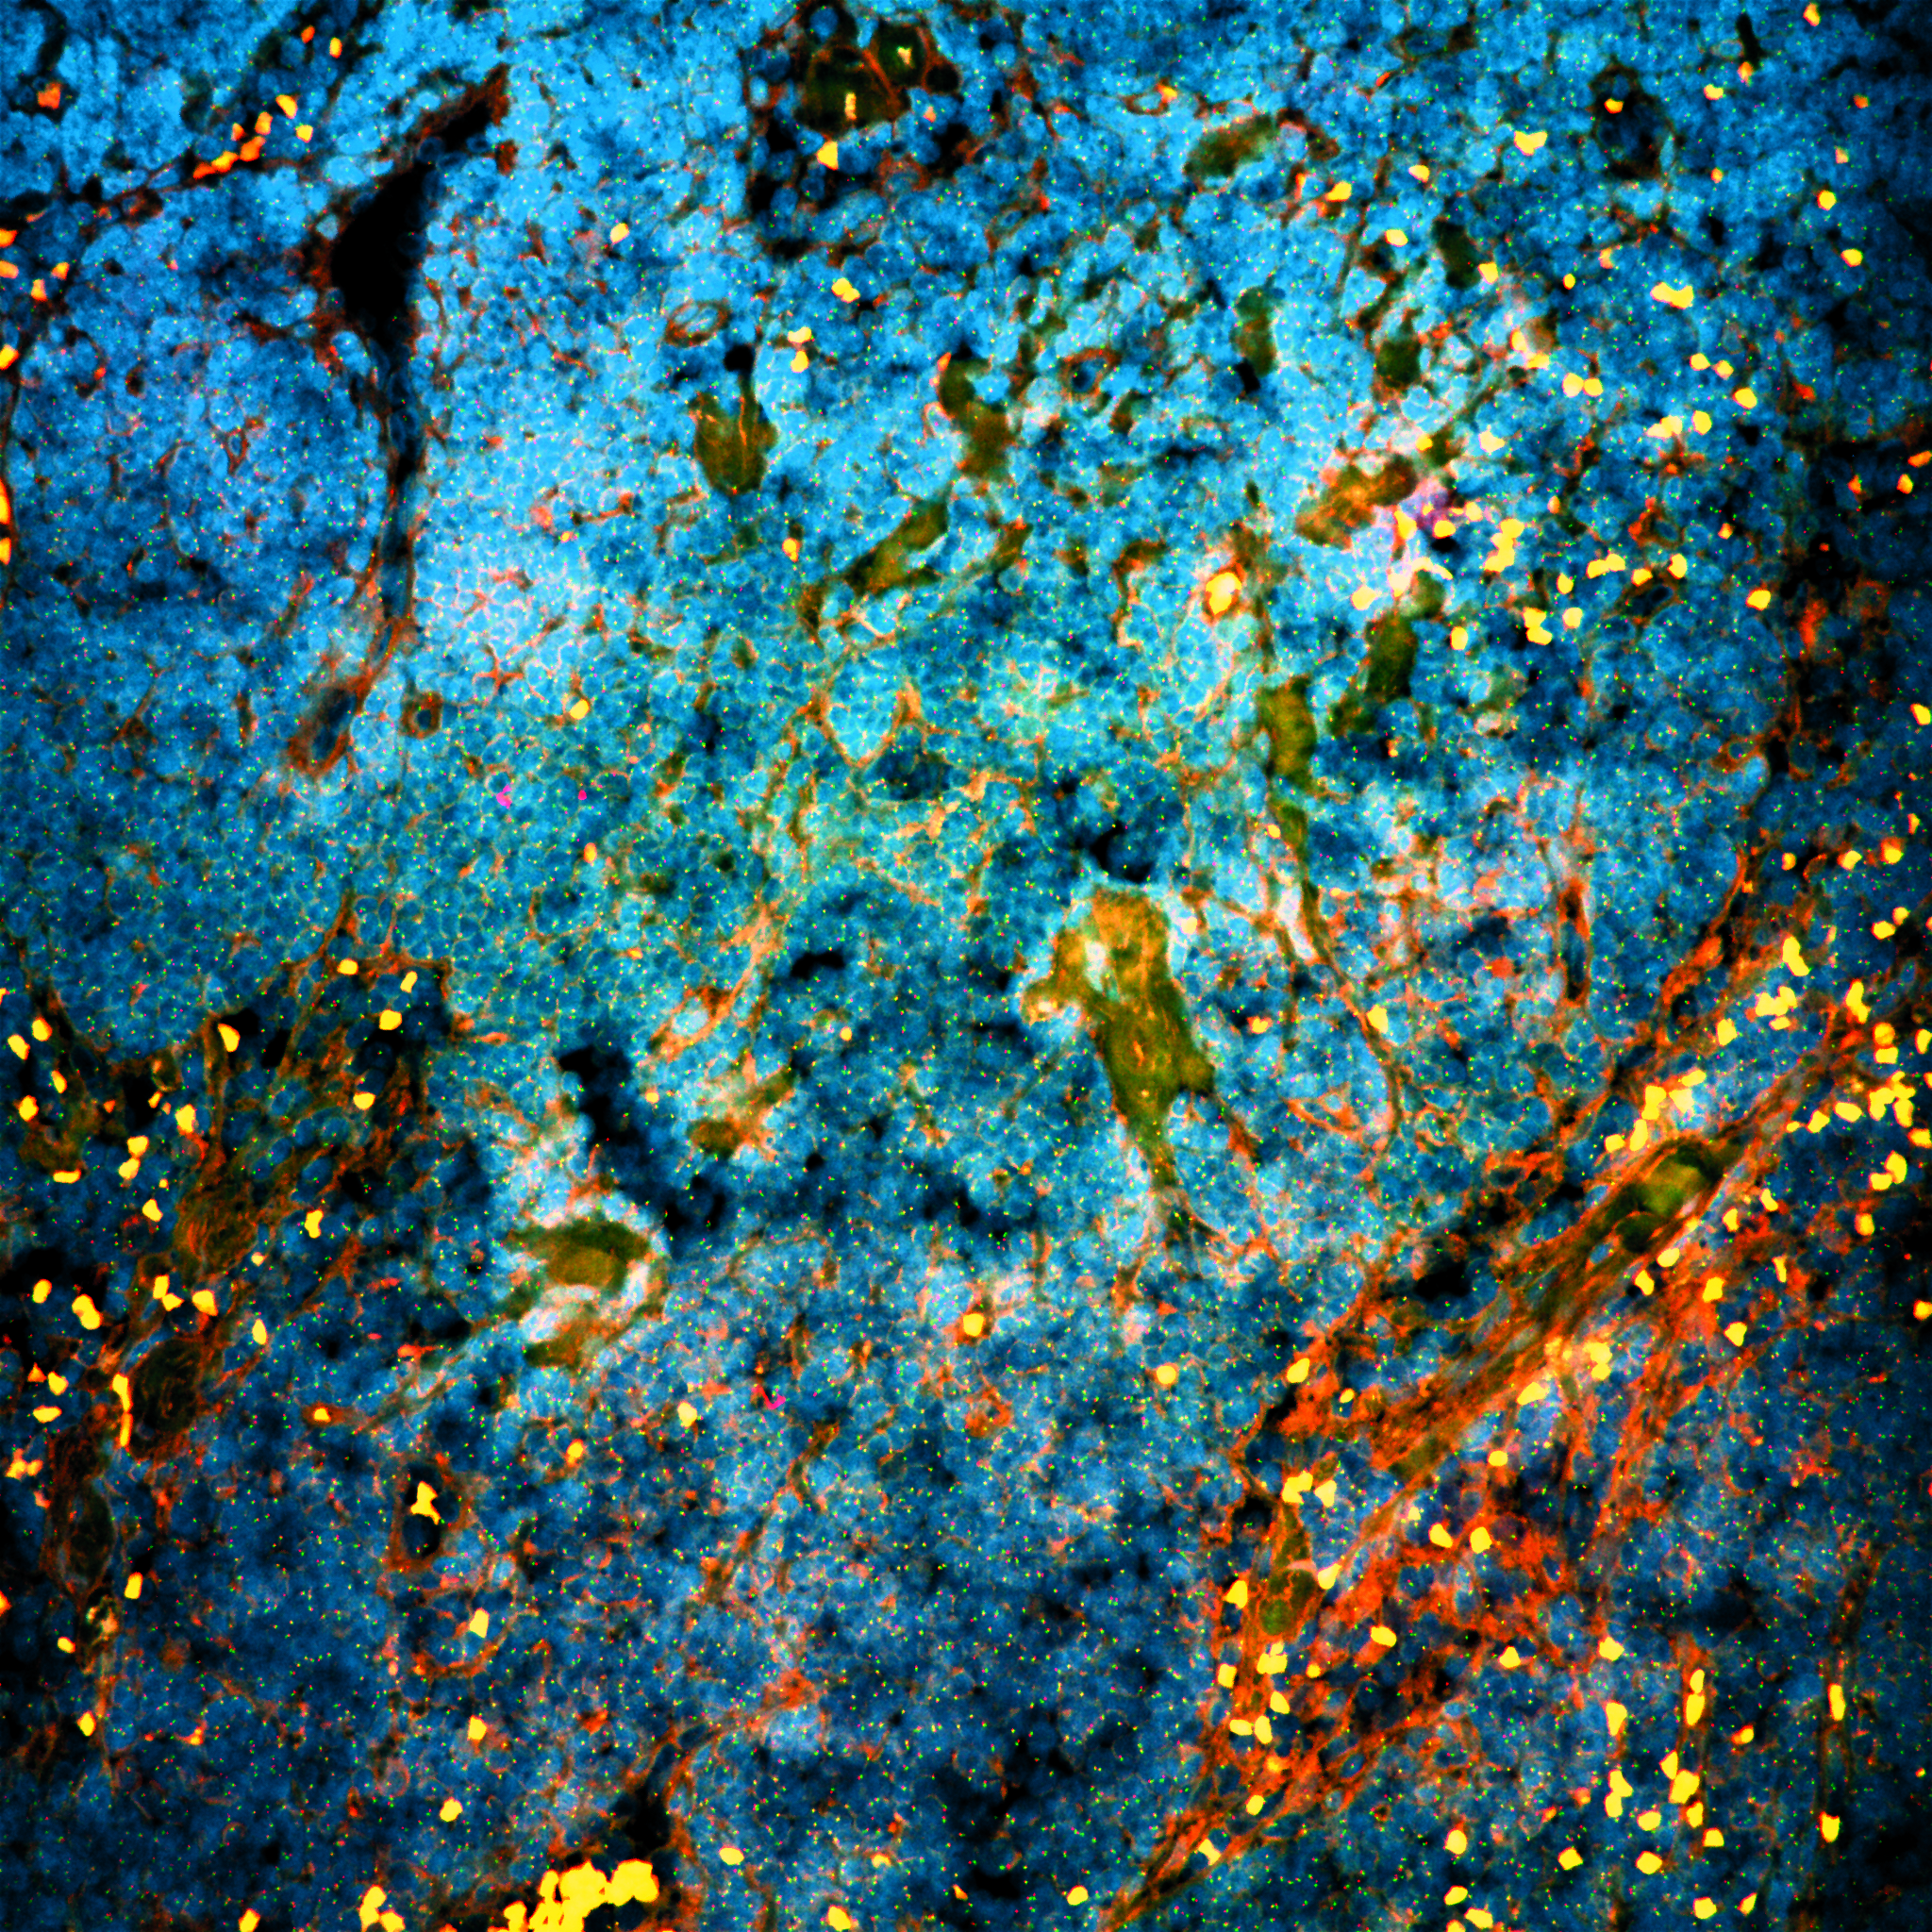

In order to find the vulnerabilities of cancer cells and treat cancer, we need to understand the biology of cancer. How do cancer cells differ from healthy cells, and how do they interact with their environment, or with therapies?

How does a cell deal with damage and interventions and how can we exploit this knowledge to optimize treatment?

How do various cell types in the body affect the development of cancer and its response to treatment?